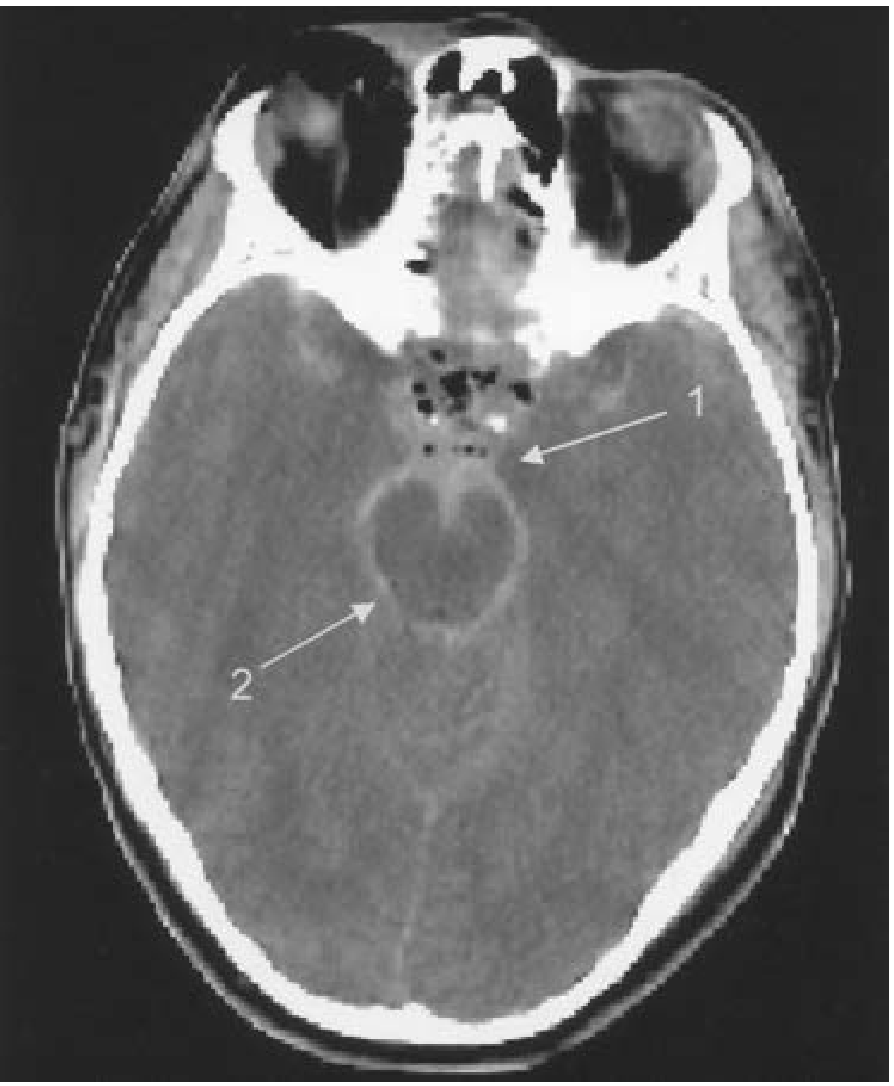

SAH — Blood filling cisterns and sulci

SAH CT — blood in prepontine cistern (arrow 1) and ambient cistern (arrow 2)

CT scan demonstrating subarachnoid hemorrhage — arrow 1 = prepontine cisternal blood, arrow 2 = blood in the ambient cistern. (Tintinalli's Emergency Medicine)

• Shape: Diffuse — fills sulci, cisterns (sylvian fissure, interhemispheric fissure, basal cisterns)

• Location: Spreads throughout subarachnoid space; aneurysmal SAH often at base of brain

• Density: Hyperdense in sulci and cisterns ("star sign" or basal cistern hyperdensity)

• Can cross suture lines (because blood is in CSF, not a mass)

• CT may be negative in ~15% of SAH within 12–24h → LP required if CT negative and clinical suspicion high (xanthochromia after 2–4 hrs)